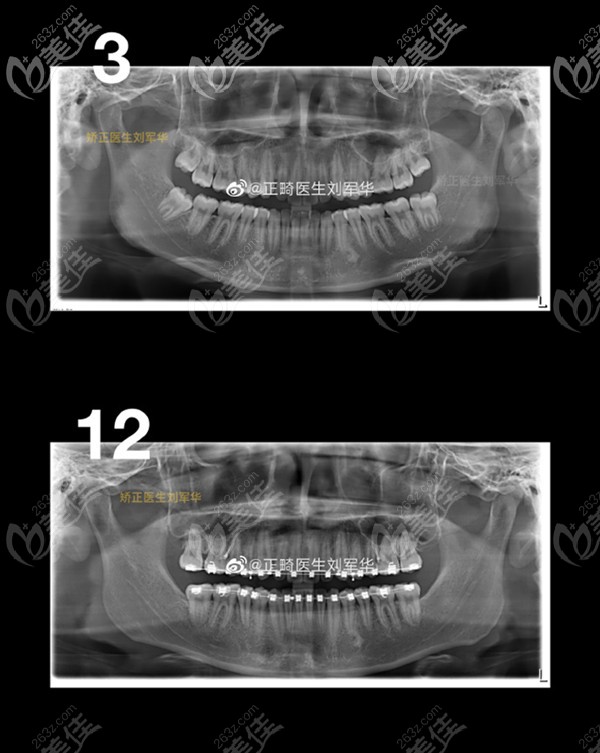

转眼我都快21岁了,看了ct对比,我才感觉到这三年的“苦”没白吃!牙齿整齐的特别明显,也不拥挤了。

支抗钉听起来吓人,但在嘴里存在的时间久了就感觉不到了,当时经过经过五个月的远中移动治疗,上颌磨牙的牙冠远移了3.78mm,牙根远移了3.2mm,效果还是挺明显的。